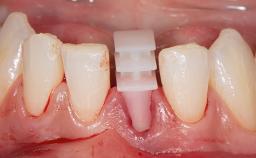

A 79-year-old female patient was referred to the Department of Periodontology of the University of Bern, Switzerland by her private dentist in May 2019. She had been rehabilitated in May 2005 with two tissue-level implants (Institut Straumann AG, Basel Switzerland) at sites 13 and 15, supporting a three-unit cemented fixed dental prosthesis (FDP). The metal-ceramic FDP had been cemented permanently with a glass-ionomer cement (Ketac Cem; 3M ESPE, Seefeld, Germany). Implant 13 had been diagnosed with peri-implant mucositis by the referring dentist in the course of regular supportive therapy. The patient was in good general health, did not smoke, and exhibited good self-performed plaque control.